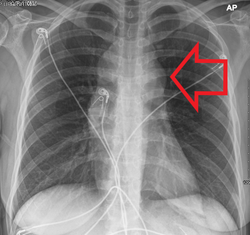

Diagram showing common sites where lymphoma spreads

After a diagnosis and before treatment, a cancer is staged. This refers to determining if the cancer has spread, and if so, whether locally or to distant sites. Staging is reported as a grade between I (confined) and IV (spread). The stage of a lymphoma helps predict a patient's prognosis and is used to help select the appropriate therapy.[43]

The Ann Arbor staging system is routinely used for staging of both HL and NHL. In this staging system, I represents localized disease contained within a lymph node group, II represents the presence of lymphoma in two or more lymph nodes groups, III represents spread of the lymphoma to lymph nodes groups on both sides of the diaphragm, and IV indicates spread to tissue outside the lymphatic system. Different suffixes imply involvement of different organs, for example S for the spleen and H for the liver. Extra-lymphatic involvement is expressed with the letter E. In addition, the presence of B symptoms (one or more of the following: unintentional loss of 10% body weight in the last 6 months, night sweats, or persistent fever of 38 °C or more) or their absence is expressed with B or A, respectively.[44]

CT scan or PET scan imaging modalities are used to stage a cancer. PET scanning is advised for fluorodeoxyglucose-avid lymphomas, such as Hodgkin lymphoma, as a staging tool that can even replace bone marrow biopsy. For other lymphomas, CT scanning is recommended for staging.[43]